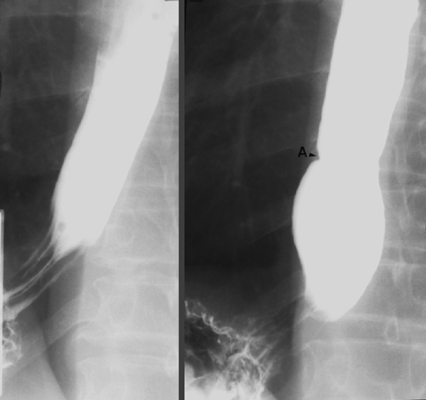

- Return to largest FOV and collimate image from side-to-side. Have the patient drink several

single swallows of dilute, non-carbonated barium through a straw.

Observe esophageal motility and also look for anatomic lesions. Take one

SC spot of the barium-distended lower esophagus and gastric

cardia during breath-holding and one SC spot of the same area during

Valsalva maneuver to evaluate for a possible sliding hiatal hernia.